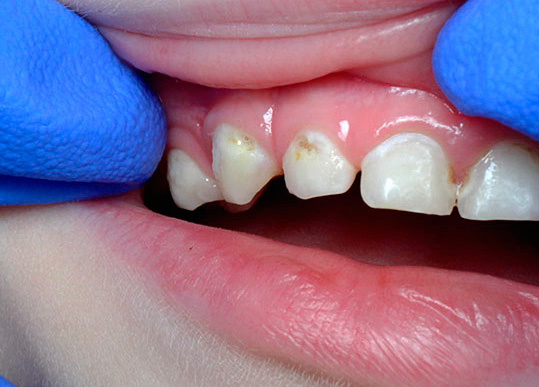

Un aspetto tipico dei denti con carie cronica è mostrato nella foto qui sotto:

Non ci sono lesioni estese dei denti e in alcuni punti le aree scure sono di dimensioni molto ridotte e spesso non attirano l'attenzione del paziente. Di solito il dolore è assente.

- La carie superficiale cronica porta alla formazione di una cavità nello smalto dei denti, ma senza danni alla dentina. Tale cavità non ha bordi sporgenti, è ampia, ben aperta, lo smalto stesso di solito si scurisce a causa della pigmentazione, ma mantiene una durezza relativamente elevata.

- La carie media cronica è caratterizzata da un'ampia cavità che colpisce la dentina. In questo corso, la cavità non ha ammorbidito la dentina, ma solo pigmentata dentina cariata. Il fondo è denso con lievi sporgenze e rugosità, che indica un processo lento nella fase di compensazione a causa della sostituzione della dentina.

Il decadimento cronico dei denti decidui si sviluppa per gli stessi motivi (un esempio è la cosiddetta carie di bottiglia). Spesso, la procrastinazione dei genitori nell'abituare il bambino all'igiene orale porta alla comparsa di focolai della malattia, che potrebbero essere evitati se si osservassero le regole elementari: regolare spazzolatura e risciacquo della bocca dopo aver mangiato.

Inoltre, la carie cronica nei bambini spesso non viene percepita dai genitori come una malattia in generale. Le lesioni cariate separate sono attribuite al fascino dei bambini con i dolci e molti genitori non prestano attenzione alla prevenzione e al trattamento, perché credono che se i denti del bambino cadono ancora, non vale la pena torturare il bambino dal dentista e spendere soldi per le cure. Di conseguenza, le misure necessarie non vengono prese in tempo e, di conseguenza, le singole lesioni diventano croniche.